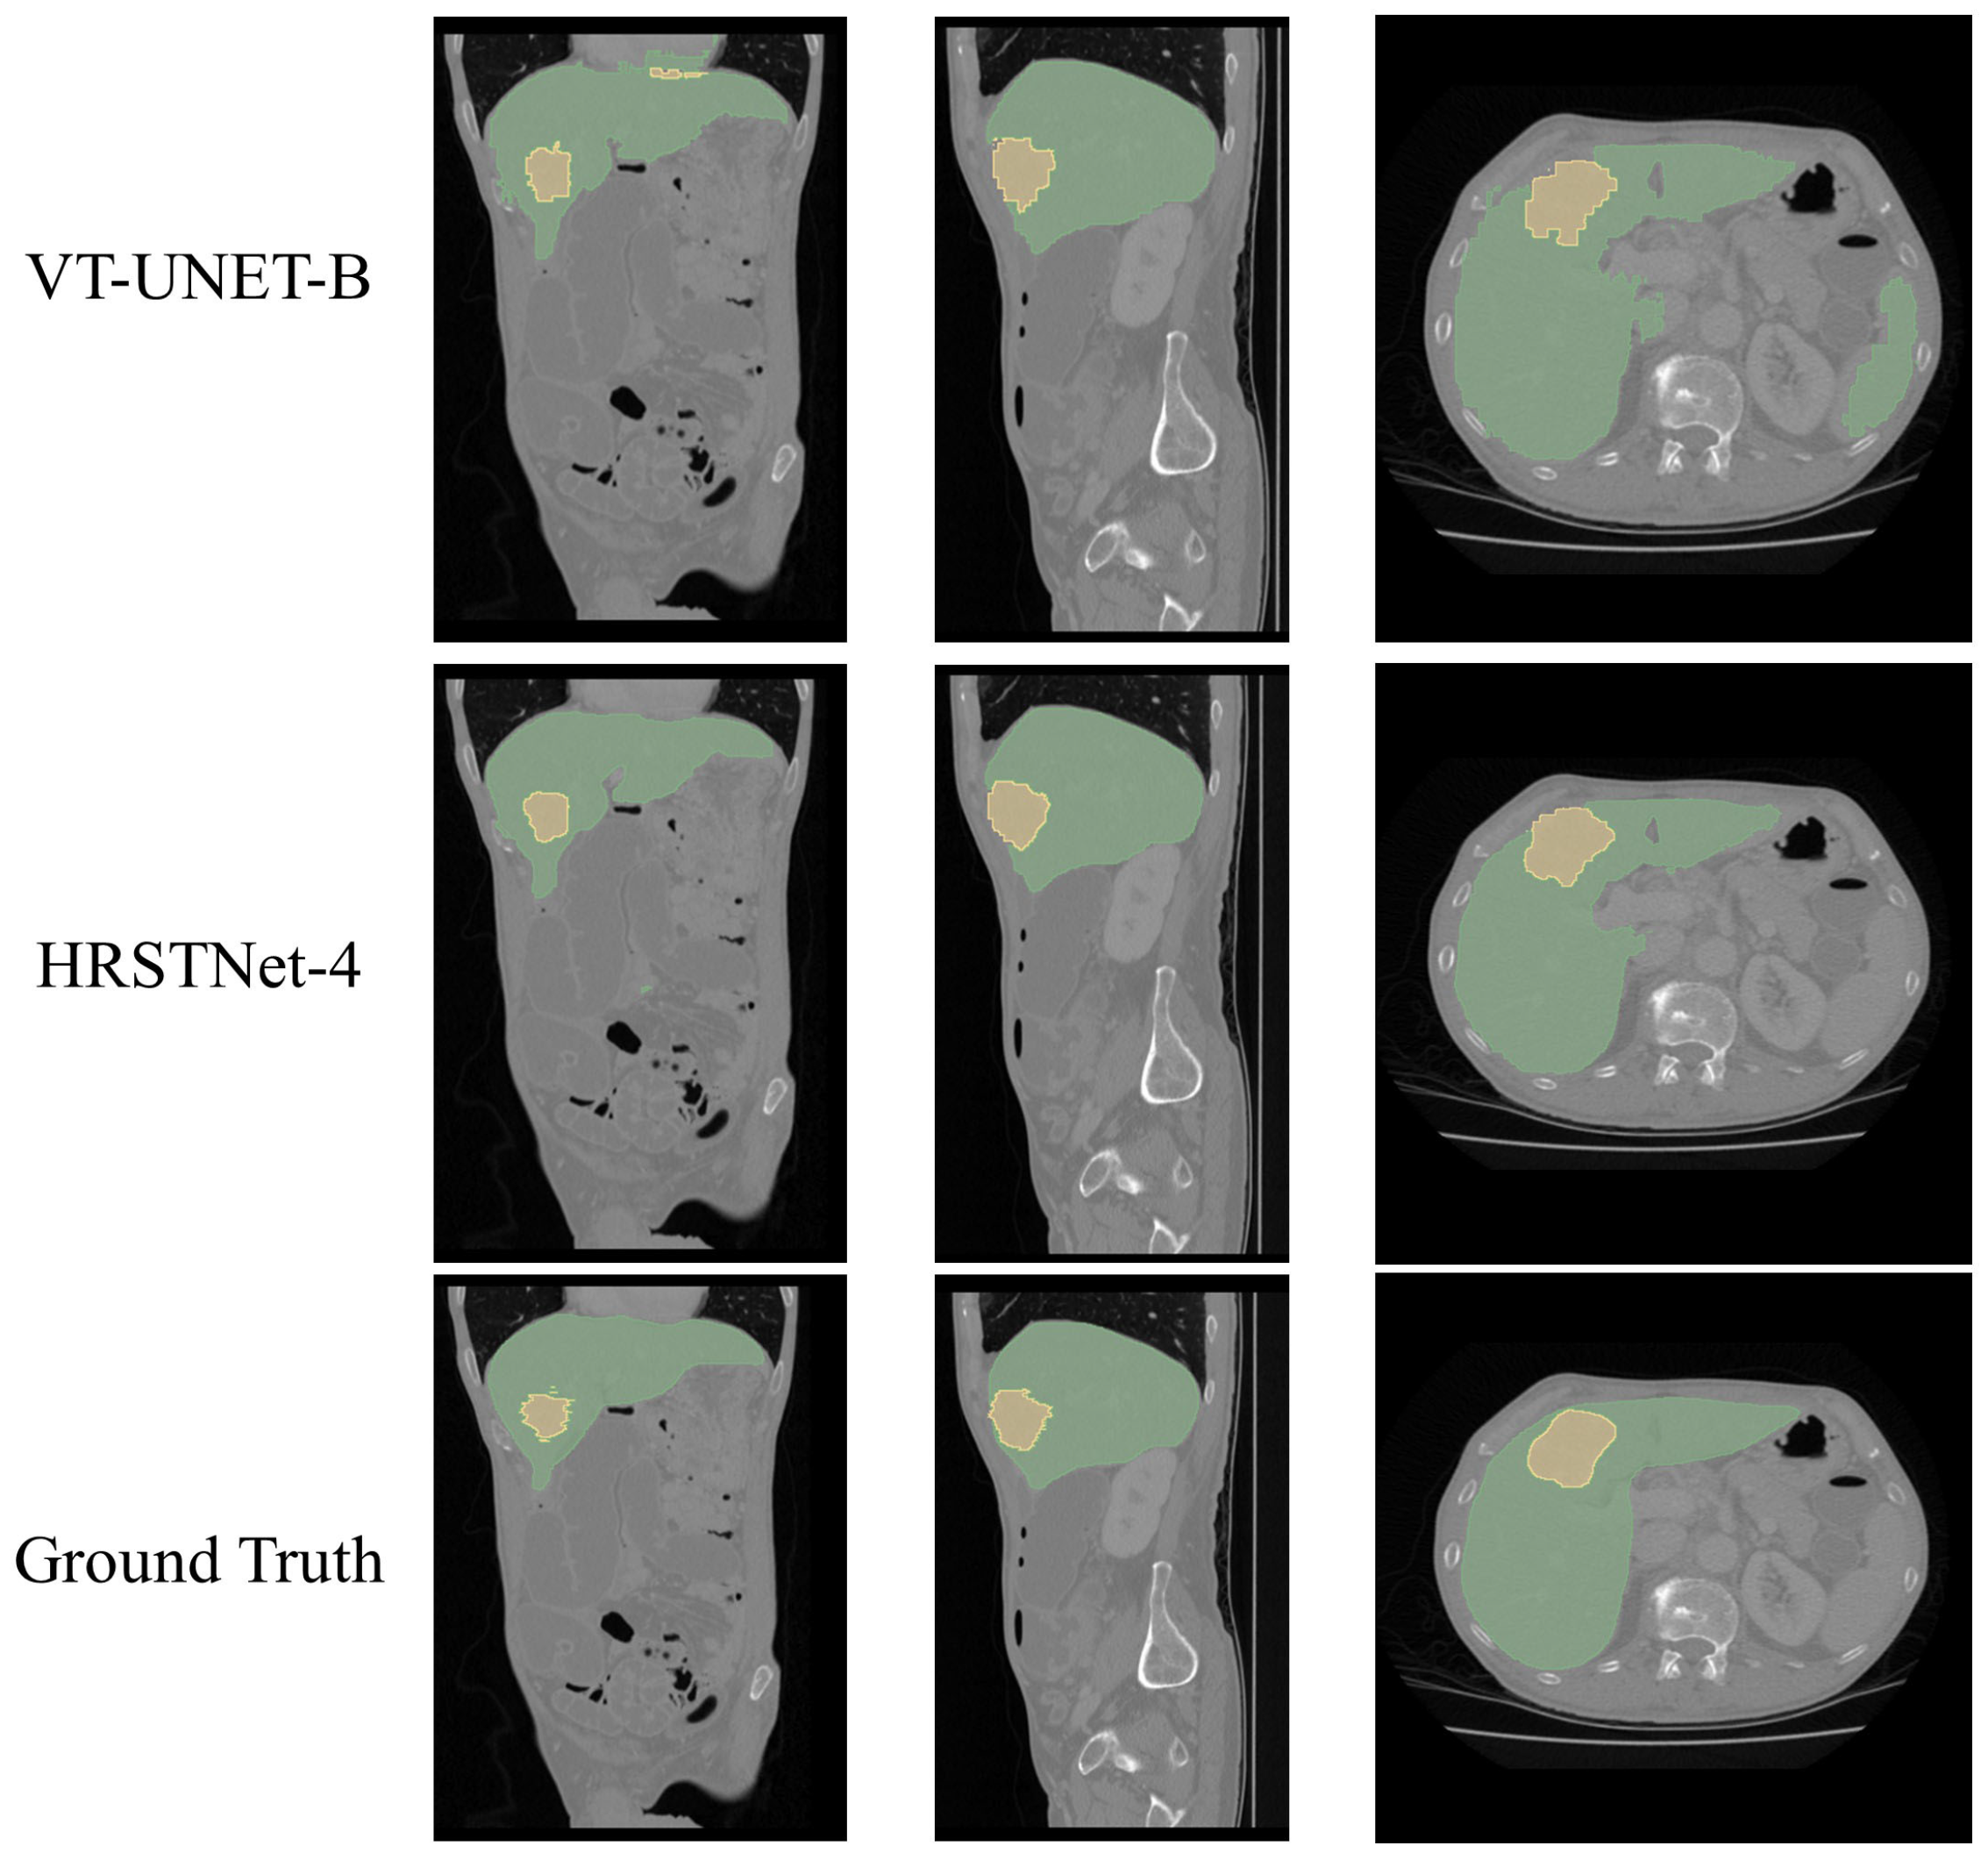

4.5. Experimental Results on the MSD Liver Dataset

| 3D UNet [11] | 92.67 | 34.92 | 63.80 |

| nnFormer [12] | 89.43 | 31.84 | 60.63 |

| VT-UNet-B [9] | 92.84 | 35.69 | 64.26 |

| HRSTNet-2 | 79.40 | 40.75 | 60.07 |

| HRSTNet-3 | 82.40 | 45.23 | 63.81 |

| HRSTNet-4 | 80.81 | 41.36 | 61.09 |